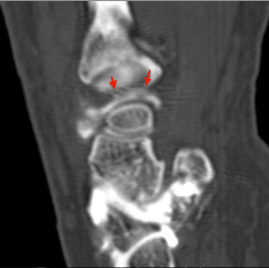

B et C - Arthro-scanner du poignet, coupe sagittale et axiale : Etendue antéro-postérieure de la zone de désinsertion du disque articulaire (flêche rouge).

Fissuration communicante (Classe 1A) du ligament triangulaire.